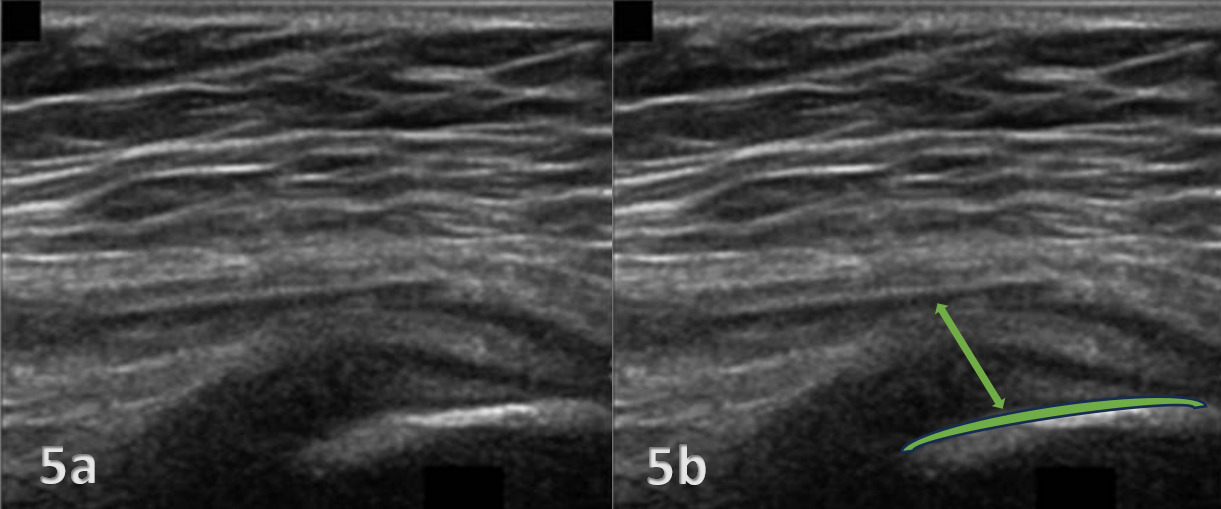

The evaluation of the gluteus medius tendon with MSKUS begins with the patient in a lateral decubitus or standing position, targeting the lateral aspect of the hip. The normal gluteus medius tendon appears as a fan shaped fibrillar structure composed of hyperechoic, striated fascicles with bright, linear bands running within the muscle.2 Pathological changes such as tendinopathy are characterized by hypoechoic (darker) regions within the tendon, tendon thickening, and loss of the normal fibrillar pattern. Tears are identified by discontinuity in the tendon fibers, with partial tears showing as anechoic (black) areas and complete tears as a full separation of the tendon from its insertion.